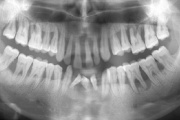

Parodontiit

Luukadu agressiivse parodontiidiga patsiendil

Agressiivse parodontiidi kahjustused rasedal naispatsiendil

GAgP 25 aastasel suitsetaval patsiendil